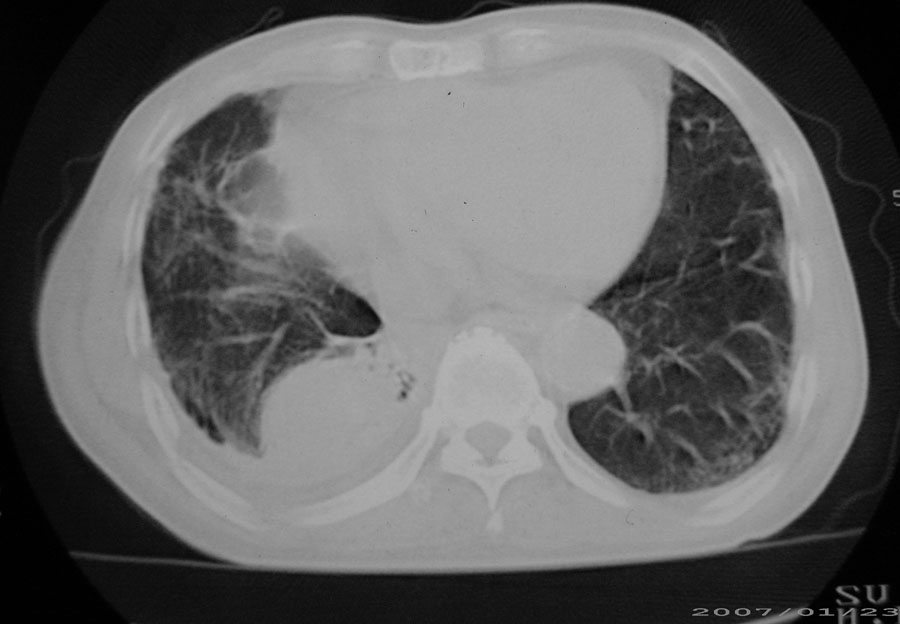

以下是引用天南地北在2007-1-24 18:00:00的发言:[br]1:右下肺内基底段类椭圆性肿快影:考虑1:右下球形肺炎2:右下肺隔离症,建议抗炎治疗后复查。[br]2:右肺及左下肺感染,右侧少量胸腔积液。

以下是引用hhcckk在2007-1-24 18:11:00的发言:[br]病灶周围胸膜反应比较明显,考虑炎症可能性大点,病人年龄较大,病灶成块状,肿瘤也不能排除,可可西里老师看片子的确很仔细,隔离肺暂时我觉得证据的说服力不大,上下层面显示条状影范围较长,可能是增厚的胸膜,可以做个增强鉴别一下